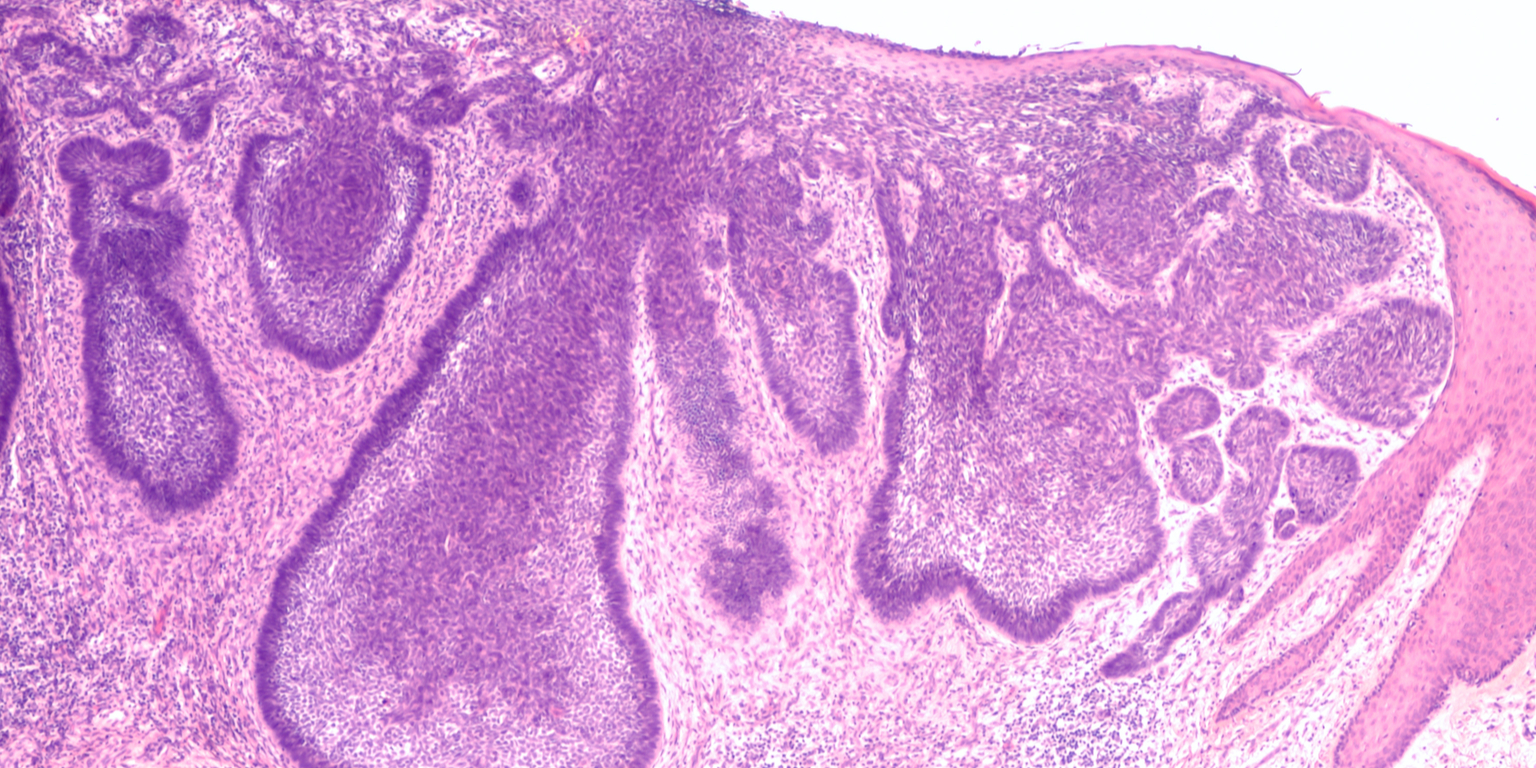

¿Qué es un carcinoma basal o epitelioma basocelular?